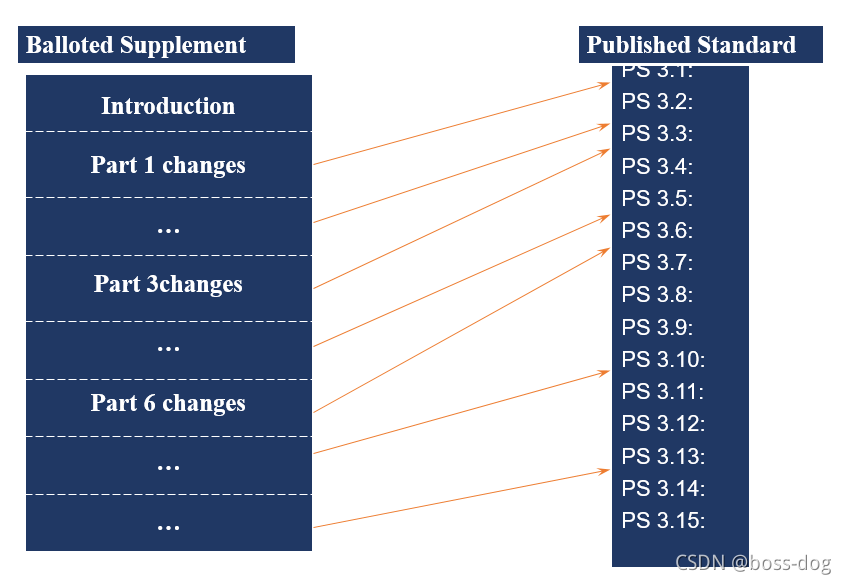

整个DICOM标准概述

- PS 3.1: Introduction and Overview (简介和概述)

- PS 3.2: Conformance(一致性)

- PS 3.3: Information Object Definitions (信息对象定义)

- PS 3.4: Service Class Specifications (服务等级规范 )

- PS 3.5: Data Structure and Encoding (数据结构与编码)

- PS 3.6: Data Dictionary (数据字典)

- PS 3.7: Message Exchange (消息交换)

- PS 3.8: Network Communication Support for Message Exchange (对消息交换的网络通信支持)

- PS 3.9: Point‑to‑Point Communication Support for Message Exchange(用于消息交换的点对点通信支持)

- PS 3.10: Media Storage and File Format for Data Interchange(数据交换的媒体存储和文件格式)

- PS 3.11: Media Storage Application Profiles(数据交换的媒体存储和文件格式)

- PS 3.12: Storage Functions and Media Formats for Data Interchange(数据交换的存储功能和媒体格式)

- PS 3.13: Print Management Point-to-Point Communication Support(打印管理点对点通信支持)

- PS 3.14: Grayscale Standard Display Function(灰度标准显示功能)

- PS 3.15: Security Profiles(安全配置文件)

- PS 3.16: Content Mapping Resource (2001)(内容映射资源(2001))

DICOM Conformance Statement(DICOM图片一致性声明):相当于每一台设备不同的型号都需要发布声明,声明里面包含了每一个tag,每个DICOM tag里面代表了定义、类型、值等等,只有发布了Conformance Statement才代表生产的每一台设备、扫描仪出来的图片是符合DICOM要求的。 - 第2部分中指定的格式和内容

- 每个声明的DICOM实现都需要“如果没有一致性声明,那就不是DICOM。”

- 一致性声明的目标受众是工程师,而不是客户。

Network Communication Support(Part 3.8)基于TCP/IP网络协议。